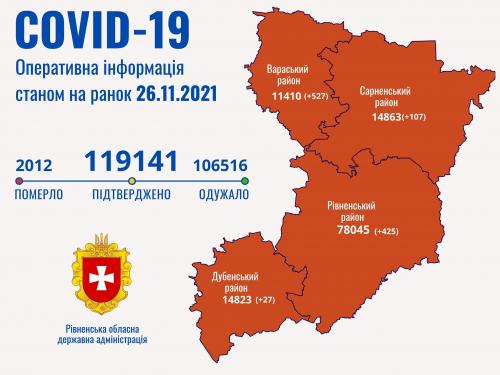

Пів тисячі - у важкому стані, 9 жителів Рівненщини померли за добу від коронавірусу